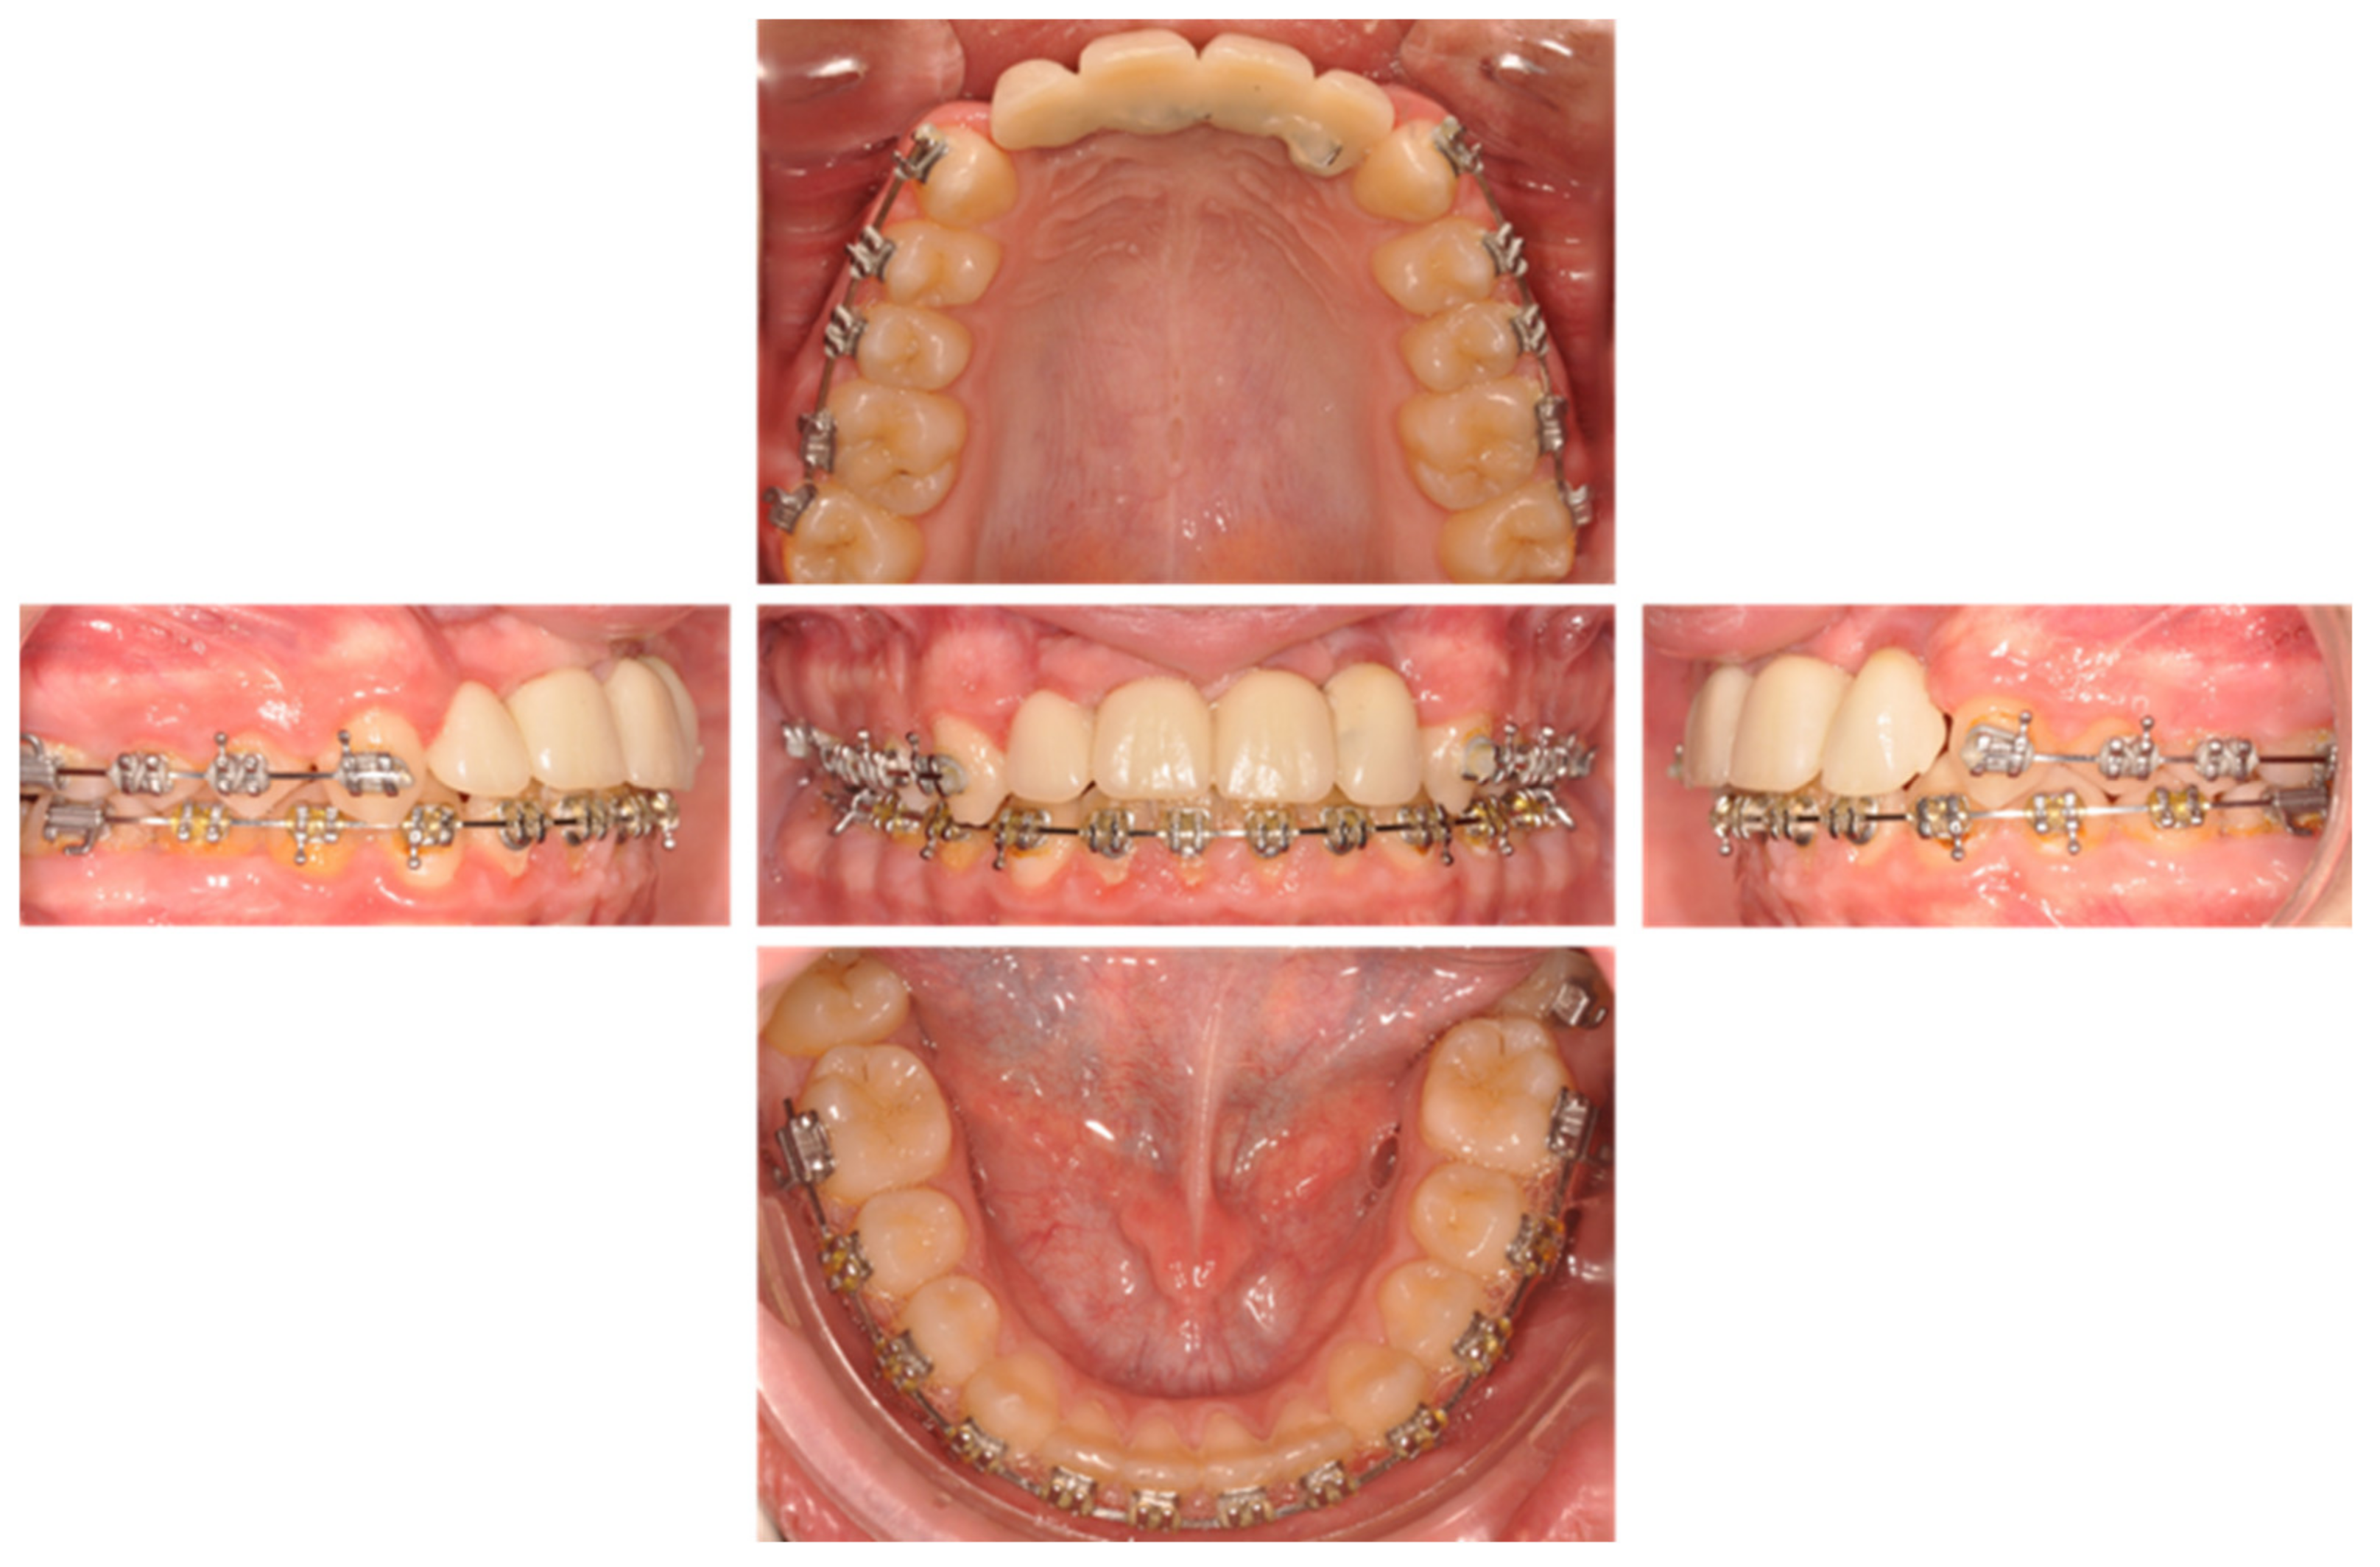

| May 2019: Orthodontic treatment for skeletal class II | Avulsion | |||

| Maintaining space for future implant replacement with resin crown temporization on the orthodontic arch | ||||

| Figure 8 | ||||